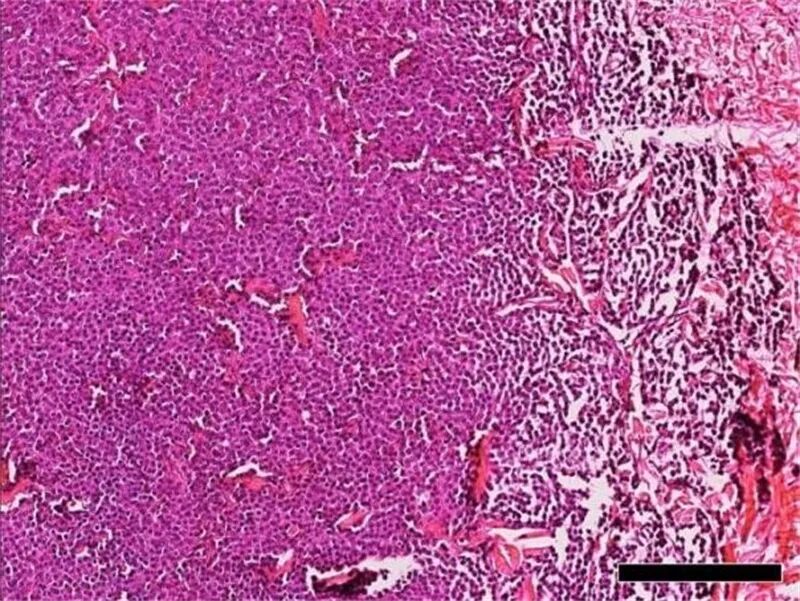

Fig. 1 肿瘤团块不具包被且与周围组织无明显界线。(H&E 染色,bar = 500 μm)

Fig. 2 肿瘤团块由高密度、呈片状排列的肿瘤细胞所组成。(H&E 染色, bar = 200 μm)